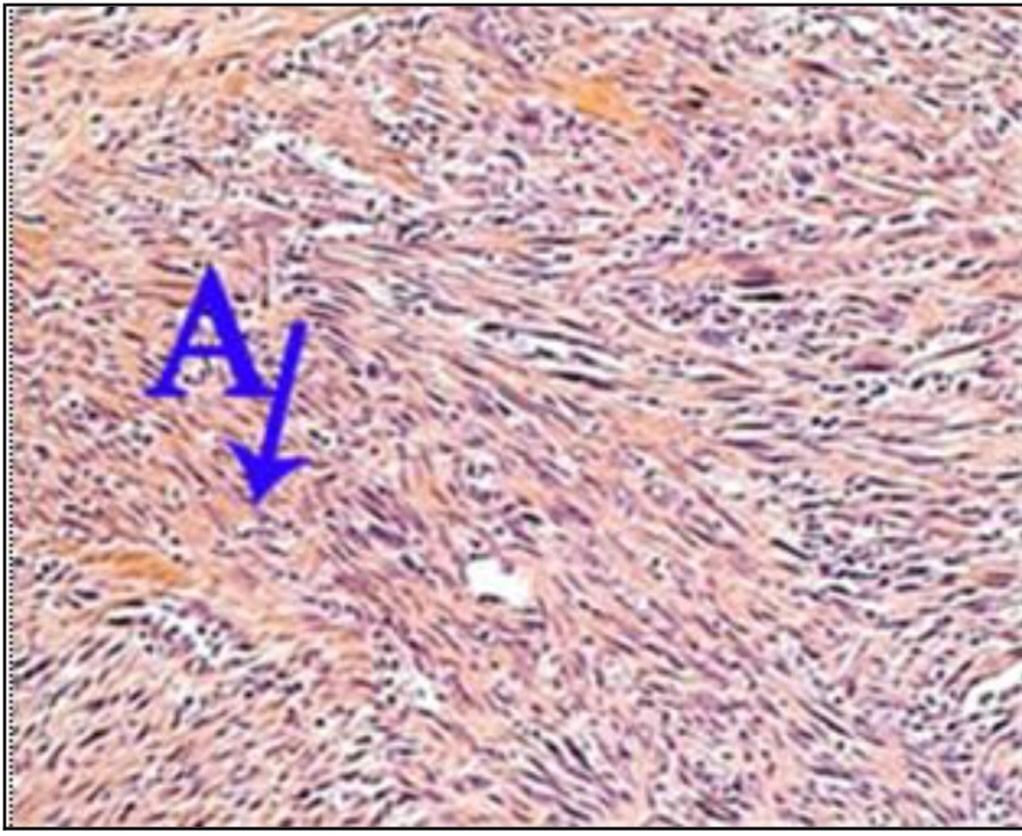

Question 41

Question

What is the correct answer at point A?

Answer

• - faisceaux entrecroisés

• - endomysium

• - léiomyocyte atypique

• - noyau atypique

• - mitose anormale

Question 42

What is the correct answer at point B?